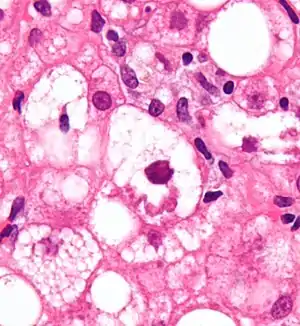

| Micrograph showing a Mallory body, a histopathologic finding associated with alcoholic hepatitis. H&E stain. | |

- Mallory's hyaline body – a condition where pre-keratin filaments accumulate in hepatocytes. This sign is not limited to alcoholic liver disease, but is often characteristic.[6]

- Ballooning degeneration – hepatocytes in the setting of alcoholic change often swell up with excess fat, water and protein; normally these proteins are exported into the bloodstream. Accompanied with ballooning, there is necrotic damage. The swelling is capable of blocking nearby biliary ducts, leading to diffuse cholestasis.[6]

- Inflammation – neutrophilic invasion is triggered by the necrotic changes and presence of cellular debris within the lobules. Ordinarily the amount of debris is removed by Kupffer cells, although in the setting of inflammation they become overloaded, allowing other white cells to spill into the parenchyma. These cells are particularly attracted to hepatocytes with Mallory bodies.[6]